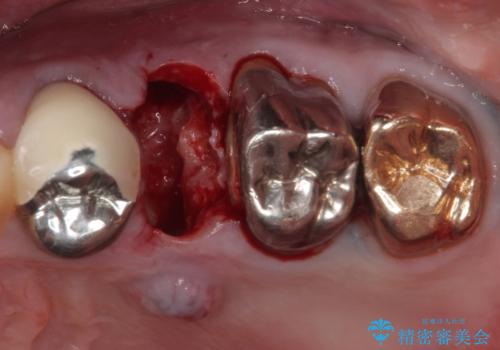

破折した奥歯 抜歯即時埋入インプラントによる補綴治療

- 舌側に膿の出口がずっと消えずに有り続けることを気にして来院された患者様です。

目視で歯根が破折していることが分かり、保存不可能と判断されたたため、抜歯即時埋入インプラントによる補綴治療を行うこととしました。